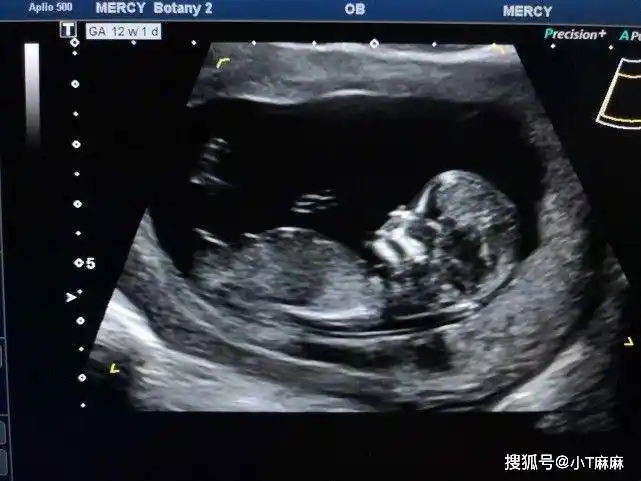

b超检查时,孕妈通过这3组数据,或许能提前知晓胎儿属性的小秘密_宝宝

b超单上的一些信息,或许透漏了宝宝的"性别",孕妈别错过_胎儿_时候

不妨看b超单上的这3个数据,准确率极高!_宝宝_进行_孕妇